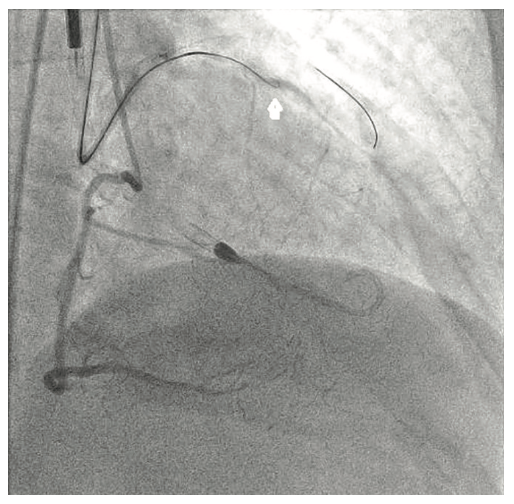

The right groin was accessed using fluoroscopic guidance. A micropuncture sheath was placed and upsized to a 7 French, 45 cm Destination sheath (Terumo) in the right groin. We accessed the right radial, but could not get good flow. Therefore, we ended up using the ulnar artery with ultrasound guidance and placed a Terumo 5/6 Slender sheath in the ulnar artery. We proceeded to access the left axillary artery. We placed a Judkins right (JR)4 catheter in the left subclavian and did a selective angiogram, documenting the location of the thoracoacromial artery and circumflex humeral (Figure 4); then using a Chiba biopsy needle (Cook), accessed the axillary artery and placed a 5-French 30 cm sheath (Cook)(Figure 5). We used the 15 cm biopsy needle to allow us a shallow angle of approach with the patient’s body habitus and to avoid “kinking” the sheath. We then switched out for the Lunderquist wire (Cook Medical), placed an 8 Fr sheath, and performed a pre-close using two Perclose devices (Abbott Vascular) (Figure 6).

Following the Perclose placement, we upsized to a 14 Fr x 13 cm Cook Medical sheath (Figures 7-8), and through that, advanced a JR catheter into the ventricle and switched out for the Impella 2.5 device (Figure 9). A JR4 and eventually, an Amplatz right (AR) mod, was used from the right ulnar to engage the RCA, and an Extra Backup (EBU) 3.5, 7 Fr (Medtronic) was used from the groin. Dual angiography was performed (Figure 10). Once the activated clotting time (ACT) was >300 seconds, the ramus was wired with a Marvel wire (Boston Scientific). We attempted to cross the LAD CTO using a Corsair (Asahi Intecc) and a Pilot 200 (Abbott Vascular). The Pilot 200 crossed, but it appeared to be in the diagonal and could not be redirected down the LAD. A Gaia second (Asahi Intecc) was able to cross into the LAD (Figure 11), and at that point, was switched out via the Corsair for a workhorse wire, a Runthrough (Terumo). An 0.9 laser (Spectranetics) was used perform laser atherectomy for a minute and a half on the LAD (Figure 12), but we could not get the catheter across. However, this allowed us to advance a balloon across the lesion and we predilated with a 1.5 mm x 20 mm Mini Trek (Abbott Vascular) and then a 2.0 mm x 20 mm balloon. The same 2.0 mm x 20 mm balloon was used in the ramus. A 2.5 mm x 15 mm AngioSculpt (Philips) was used to predilate the LAD, but on its return, the AngioSculpt became stuck and would not come back. We got it partially into the guide and then the shaft broke. We had part of the catheter in the guide and part of it in the coronary (the left main). We initiated a series of procedures to remove the AngioSculpt, first attempting use of a GuideLiner (Vascular Solutions) to envelope the balloon, but this was unsuccessful (Figure 13). The GuideLiner kept pushing the device further out. We tried trapping it; that was also unsuccessful. We were able to get a Mini Trek balloon distal, thinking it could be inflated and pulled back; that did not work. We then put the 4 wires down, wrapped the wires around and pulled back, getting it partially in the guide, but we could not get it all the way in. We got a Mini Trek down, used the GuideLiner to put a 2.0 down, and attempted an anchor technique that did not work, but this time, when we pulled the Mini Trek 2.0 back, it dislodged the balloon. The AngioSculpt was able to come in the guide and was removed without losing wire position. We rewired the ramus, performed dilation of the LAD and ramus with a 2.5 mm noncompliant balloon, and performed intravascular ultrasound (IVUS). The LAD was about 2.75 mm2 distally and the ramus was 3.0 mm2, with the left main being approximately 3.75 mm2. A double kissing (DK) crush technique was used with a 2.75 mm x 38 mm Synergy stent (Boston Scientific) to the LAD and 3.0 mm x 24 mm Synergy to the ramus; then we used proximal optimization technique (POT) with a 3.75 mm NC balloon (Medtronic) and a final kiss with 3.0 mm x 20 mm NC balloons (Figures 14-17). IVUS was used to confirm that the stents were well apposed. The Impella device was weaned and removed, keeping the sheath in. From the groin sheath, a balloon was advanced into the left subclavian and we did a dry close. We inflated an 8.0 mm x 40 mm balloon at 3 atmospheres (nominal is 6 atmospheres) (Figure 18). Once the pressure tracing from the axillary sheath side arm dropped, we were able to remove the sheath and then completed the Perclose. There was some slight track ooze (Figure 19). Therefore, we performed two 5-minute inflations with the 8.0 mm x 40 mm balloon at 3 atmospheres (nominal is 6 atmospheres), and there was complete resolution of the track ooze. No extravasation was noted (Figures 20-21). The ulnar sheath was sutured in, we made sure there were no issues overnight, and the patient was discharged the following morning.